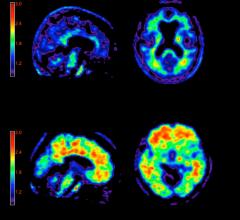

Navidea Biopharmaceuticals Inc. announced the peer-reviewed publication of results from a clinical trial of NAV4694 in healthy subjects and those with diagnosed forms of dementia. The trial assessed the performance of Navidea’s Fluorine-18 labeled amyloid imaging candidate, NAV4694, in a head-to-head comparison with the acknowledged benchmark, gold-standard amyloid imaging agent, 11C-labeled Pittsburgh Compound-B (PiB). Results demonstrated that NAV4694 displayed imaging characteristics nearly identical to those of PiB and the authors believe these results show that NAV4694 may be useful in the early and differential diagnosis of Alzheimer’s disease (AD). The study, “Head-to-Head Comparison of 11C-PiB and 18F-AZD4694 (NAV4694) for ?-Amyloid Imaging in Aging and Dementia,” was published in the current online edition of the Journal of Nuclear Medicine and will appear in the June print edition.